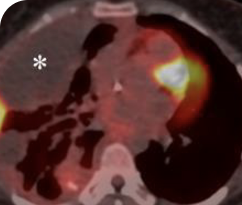

BASELINE

AFTER 2 MONTHS OF TREATMENT

56-YEAR-OLD FEMALE WITH MULTIPLE METASTASES3

PATIENT CASE:

METASTATIC, RAIa-REFRACTORY,

PAPILLARY THYROID CANCER1

- 56-year-old female with PTCa that had metastasized to multiple sites, including the brain

- Progression after first- and second-line systemic treatment

- PRa after 4 weeks on VITRAKVI® (larotrectinib); CRa after 8 weeks

- At last assessment, complete response was sustained over an 11-month period

Clinical presentation1

- Patient was assessed to have metastatic, rapidly progressive, RAl-refractory PTC based on imaging that revealed multiple metastatic sites, including the neck, mediastinum, lung, scalp, and bones

- Biopsy of a scalp lesion helped to confirm the PTC metastasis

- Metastases to the brain and liver were observed after progression on systemic treatments

VITRAKVI treatment1

- VITRAKVI 100 mg twice daily orally

Response to VITRAKVI1

- After 8 weeks on VITRAKVI, all target lesions had disappeared, demonstrating a complete response

- The complete response was sustained over 11 months of treatment with VITRAKVI

- Patient experienced Grade 1 fatigue and mild hepatic enzyme elevation

Response in primary and metastatic lesions1

MRIa imagery of the lungs. Arrow indicates large target lesion in left lung.1

SCAN 1: LUNG

MRIa imagery of the brain. Arrow indicates large target lesion in left lung.1

aMRI, magnetic resonance imaging.

Images courtesy of Dr Fabian Pitoia.